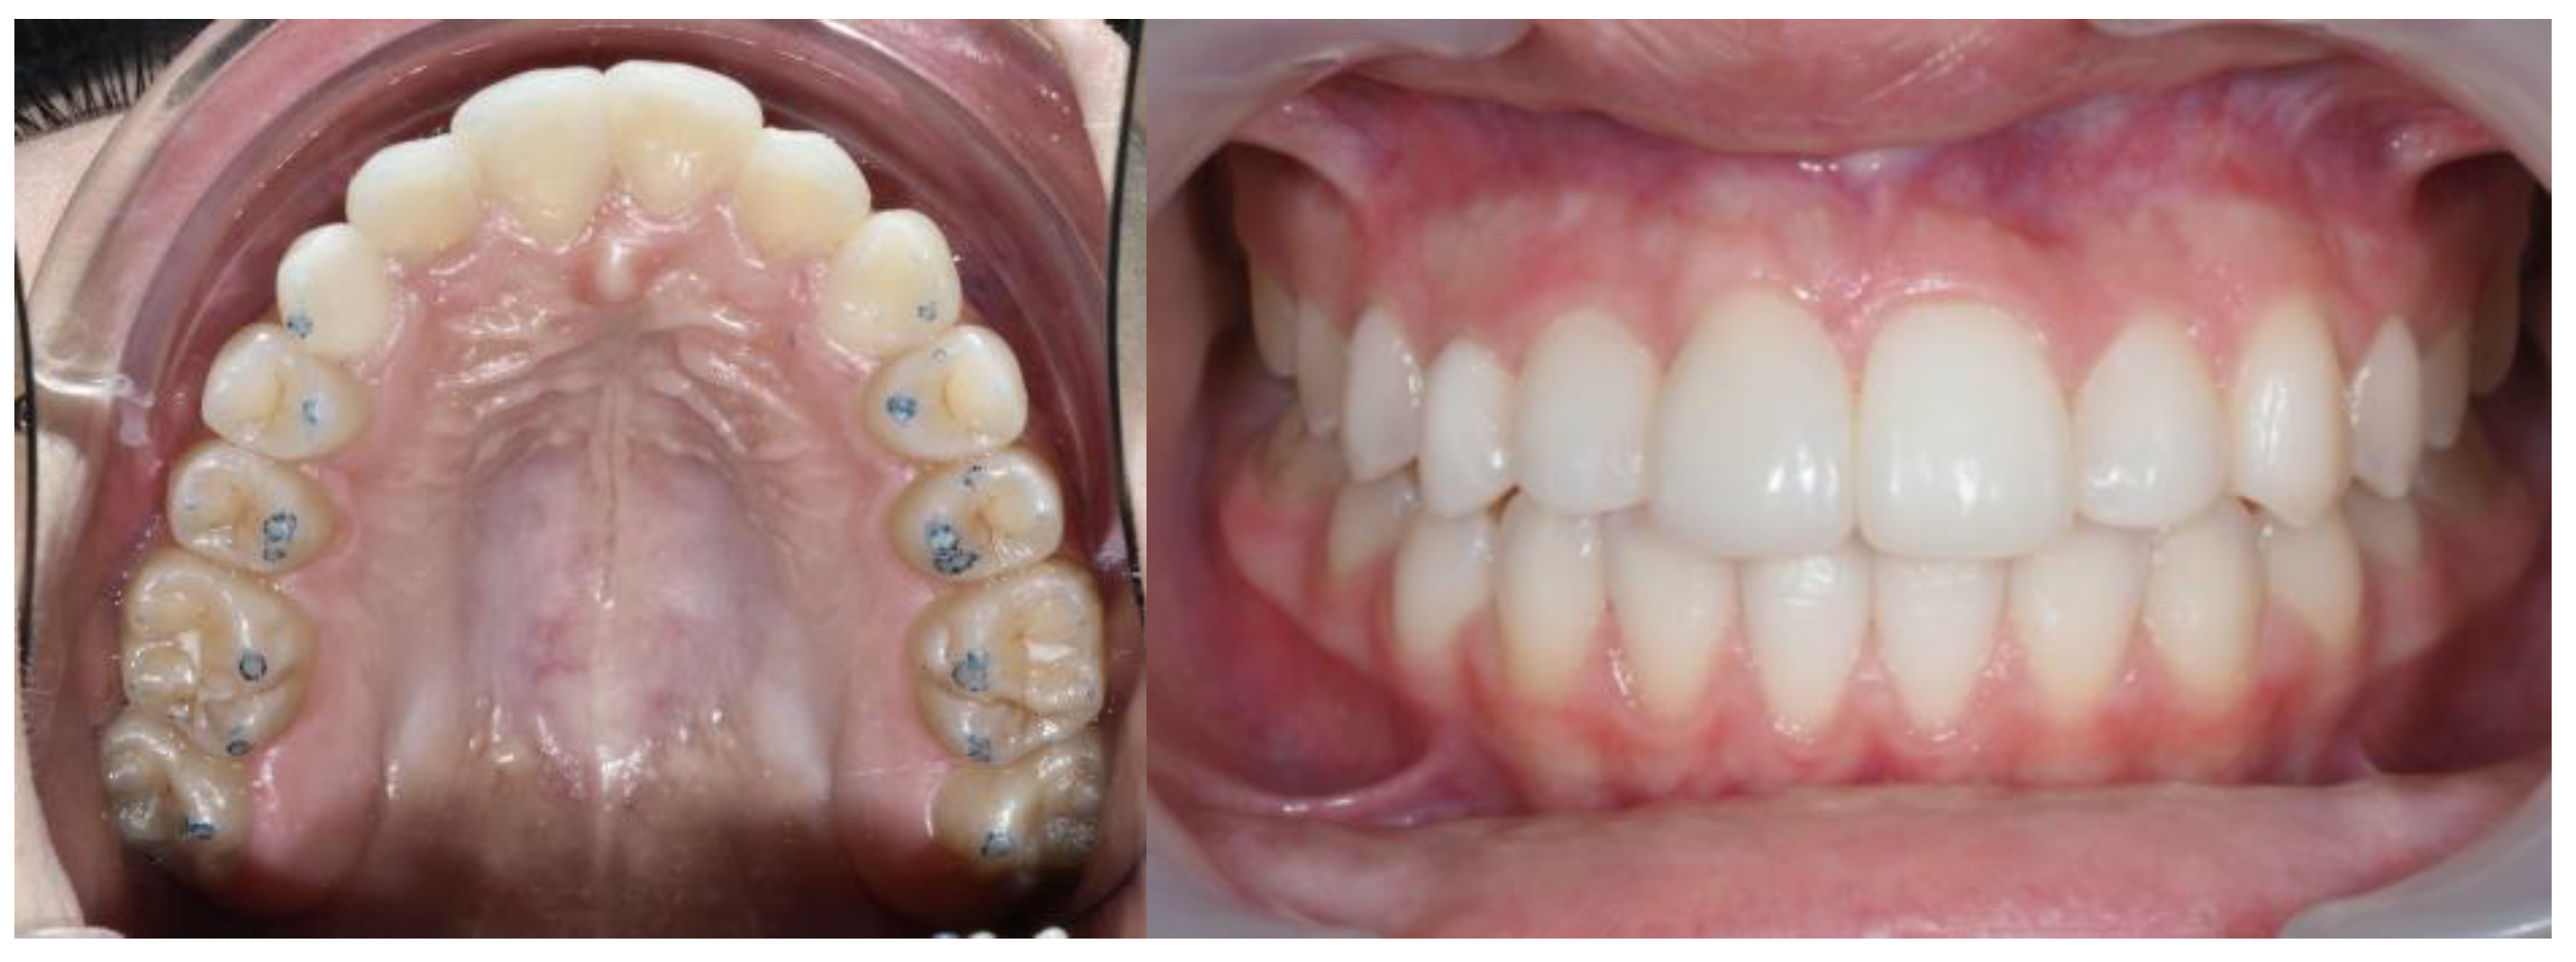

| Pinho T., Amaral R. 2025 | ♀ 13 YO | Mx.C.I1 | C | R | V (impacted) | Cl I | Maintained | -Total root resorption of tooth #11 due to the position of the ectopic canine |

3.2. Clinical Case